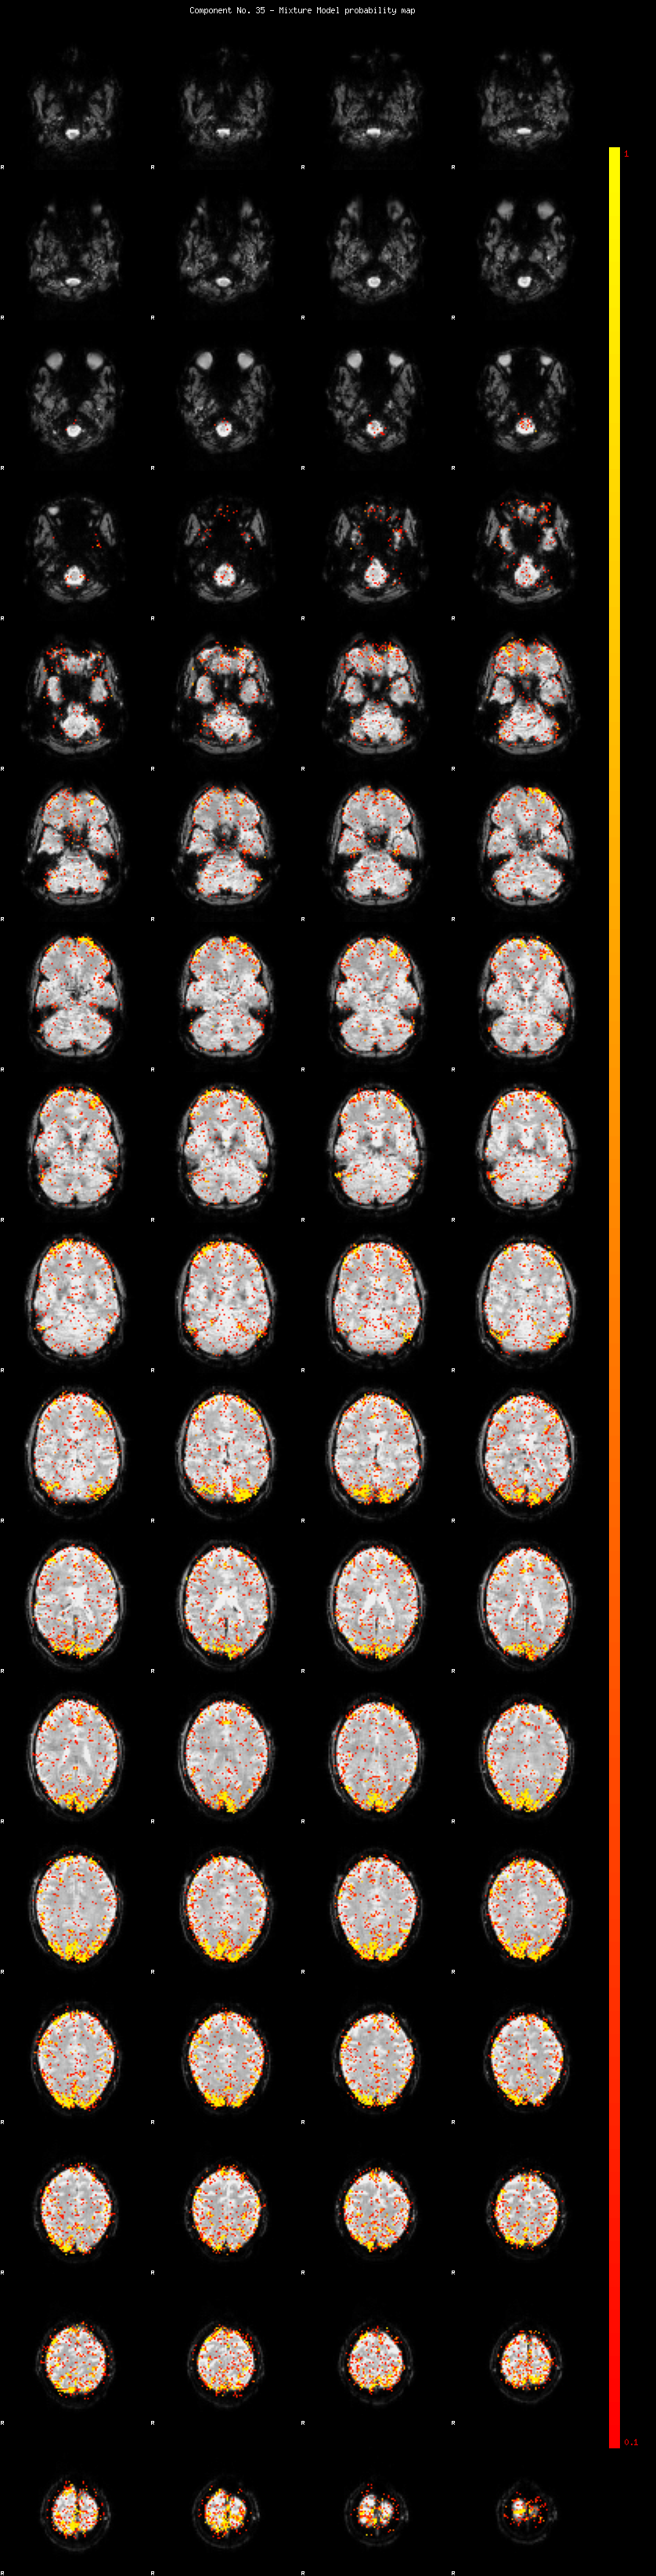

IC_35 Mixture Model fit

Means : -0.000000 3.802411 -2.670707

Vars : 1.000000 6.685658 1.459577

Prop. : 0.926124 0.050746 0.023130